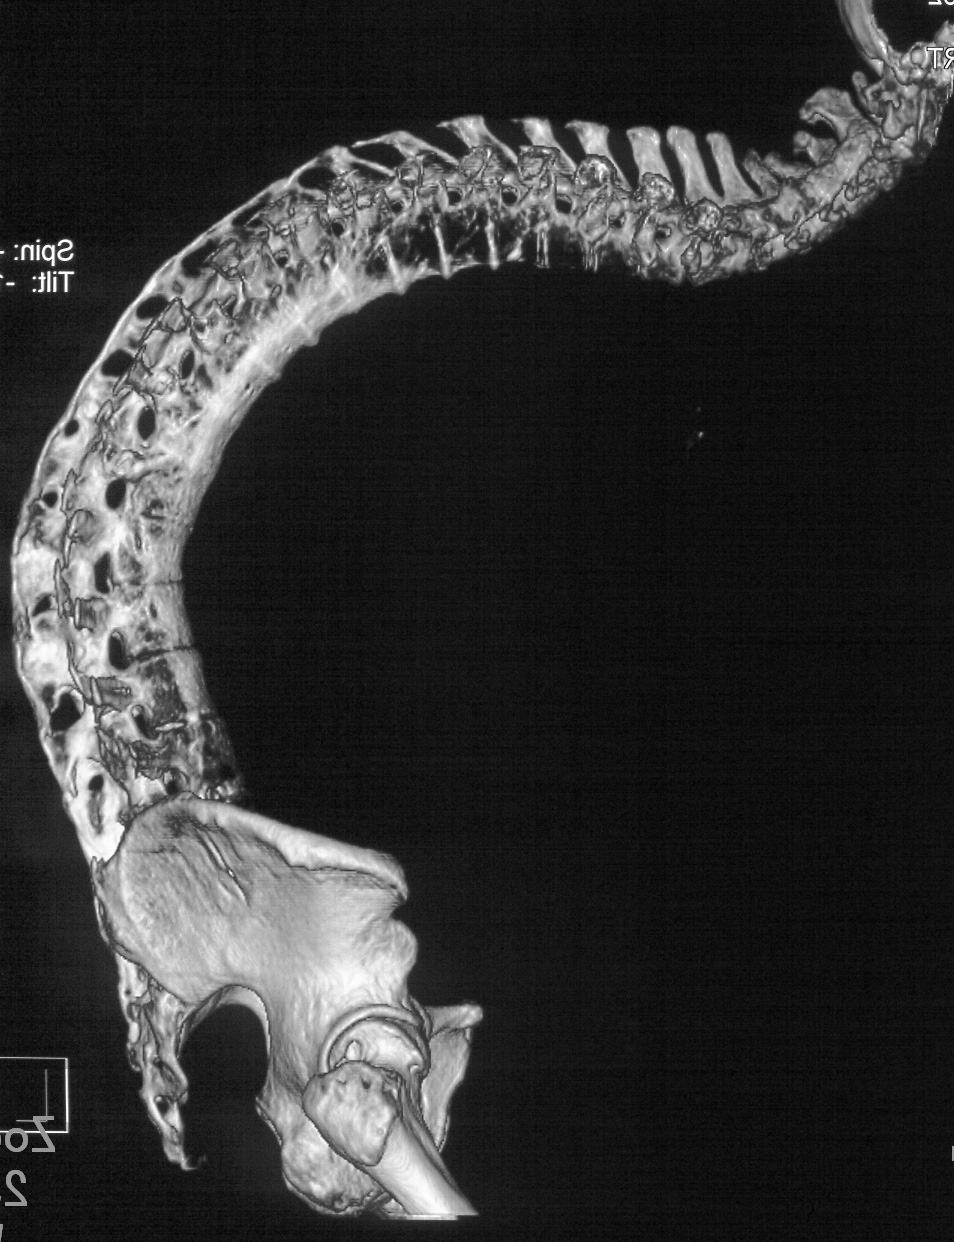

强直性脊柱炎的英文简称为AS,我们可以又把它叫做类风湿性脊柱炎 ...